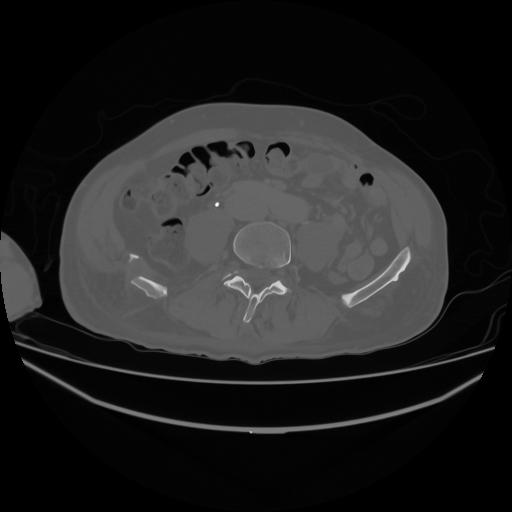

5 CUERPO,CE,Vol,1.0,CUERPO,,